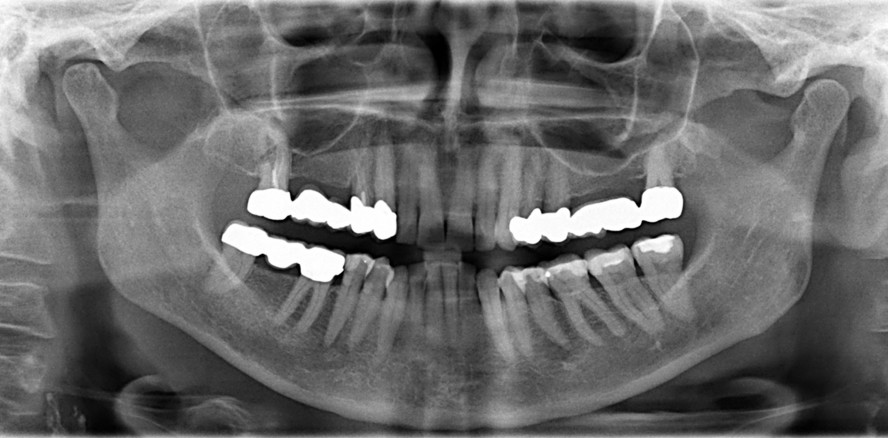

In diesem Beitrag werden die Relevanz und Erkenntnisse klinisch etablierter sowie experimenteller Möglichkeiten der Bildgebung für die zahlreichen Variationen...

In diesem Beitrag werden die Relevanz und Erkenntnisse klinisch etablierter sowie experimenteller...